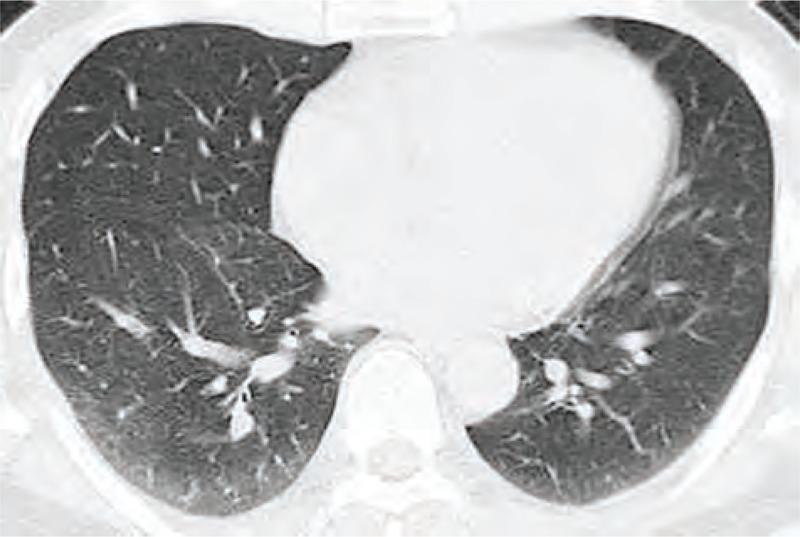

Pulmonary Langerhans cell histiocytosis (PLCH) is a rare disease with insidious onset and nonspecific manifestations. The objective of this article was to characterize the clinical manifestations and features of PLCH by retrospectively analyzing clinical data of patients with PLCH in addition to simultaneous review of literature.A retrospective analysis was conducted on clinical data of patients with PLCH (n = 7), whose conditions were diagnosed by biopsy from pulmonary tissue (n = 6) or enlarged lymph nodes in the neck (n = 1) and confirmed by PLCH typical radiological features on computed tomography (CT) scan, between January 2001 and September 2012 at the Shanghai Pulmonary Hospital, Tongji University School of Medicine, Shanghai, China. The review of published reports was made to further emphasize the clinical manifestation and radiological features of PLCH.Long history of cigarette smoking was found in 6 patients. Two patients had recurrent pneumothorax and the other 2 had pulmonary arterial hypertension (World Health Organization group 5 pulmonary hypertension), diagnosed through ultrasonic cardiogram. The nodular shadows were revealed by chest CT scan in 5 patients, cystic shadows in 5 patients, and reticular shadows in 2 patients, as major manifestations, respectively; most of the lesions were located in the middle or upper segments of the lung. The obvious shrank of lesion was found in 1 patient after completely quitting smoking.The pathogenesis of PLCH might be closely associated with smoking. The cystic or nodular lesion was the typical radiological features. Further prospective studies with large sample size are required to further validate the study results and understand the clinical characteristics of PLCH to avoid misdiagnosis.